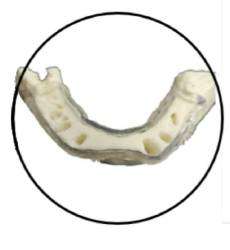

CTARS IPS has a custom made software which can able to guide an implantologist to place an implant in a predetermined surgical plan which will be more precise and accurate to the deep insight about patient anatomy and also helps in reducing the time duration and increasing patient comfort.No two patients teeth are the same. That’s why each and every CTARS IPS guide is custom made to fit your implant plan and patient’s anatomy.CTARS is available with tooth or bone (dentulous or edentulous) supported.

One Guide KIT

Pilot Drill Guided